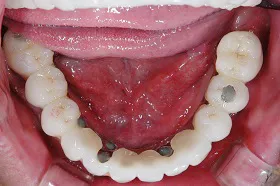

咀嚼障害のため来院されたケース(all-on-4)

60代 男性

咀嚼障害、歯茎の痛みを訴えられ、来院されました。

■治療前

■治療後

| 主訴 | かみにくい・全体的に歯茎が腫れて痛みがある 痛みがある |

| 治療方法 | 上下顎に複数本のインプラントを使用し、一体型の補綴物をセット |

| 治療期間 | 約1年 |

| 通院回数等 | 約20回 |

| 費用 | 約600万円 |

| リスク・副作用 | 補綴物が過度な力で破損するリスクがある |